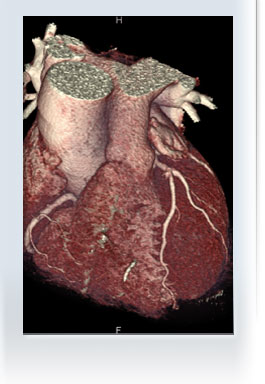

Erstmals ermöglicht uns die moderne Computertomographie(CT) die Herzkranzgefäße in beeindruckender Qualität sichtbar zu machen, ohne dass Sie sich einer aufwendigen Herzkatheter-Untersuchung unterziehen müssen.

Die Art der Ablagerungen im Bereich der Kranzgefäße lässt sich im Cardio-CT besser als im Herzkatheter beurteilen. Die Herzkranzgefäße können in verschiedenster Weise dargestellt werden.